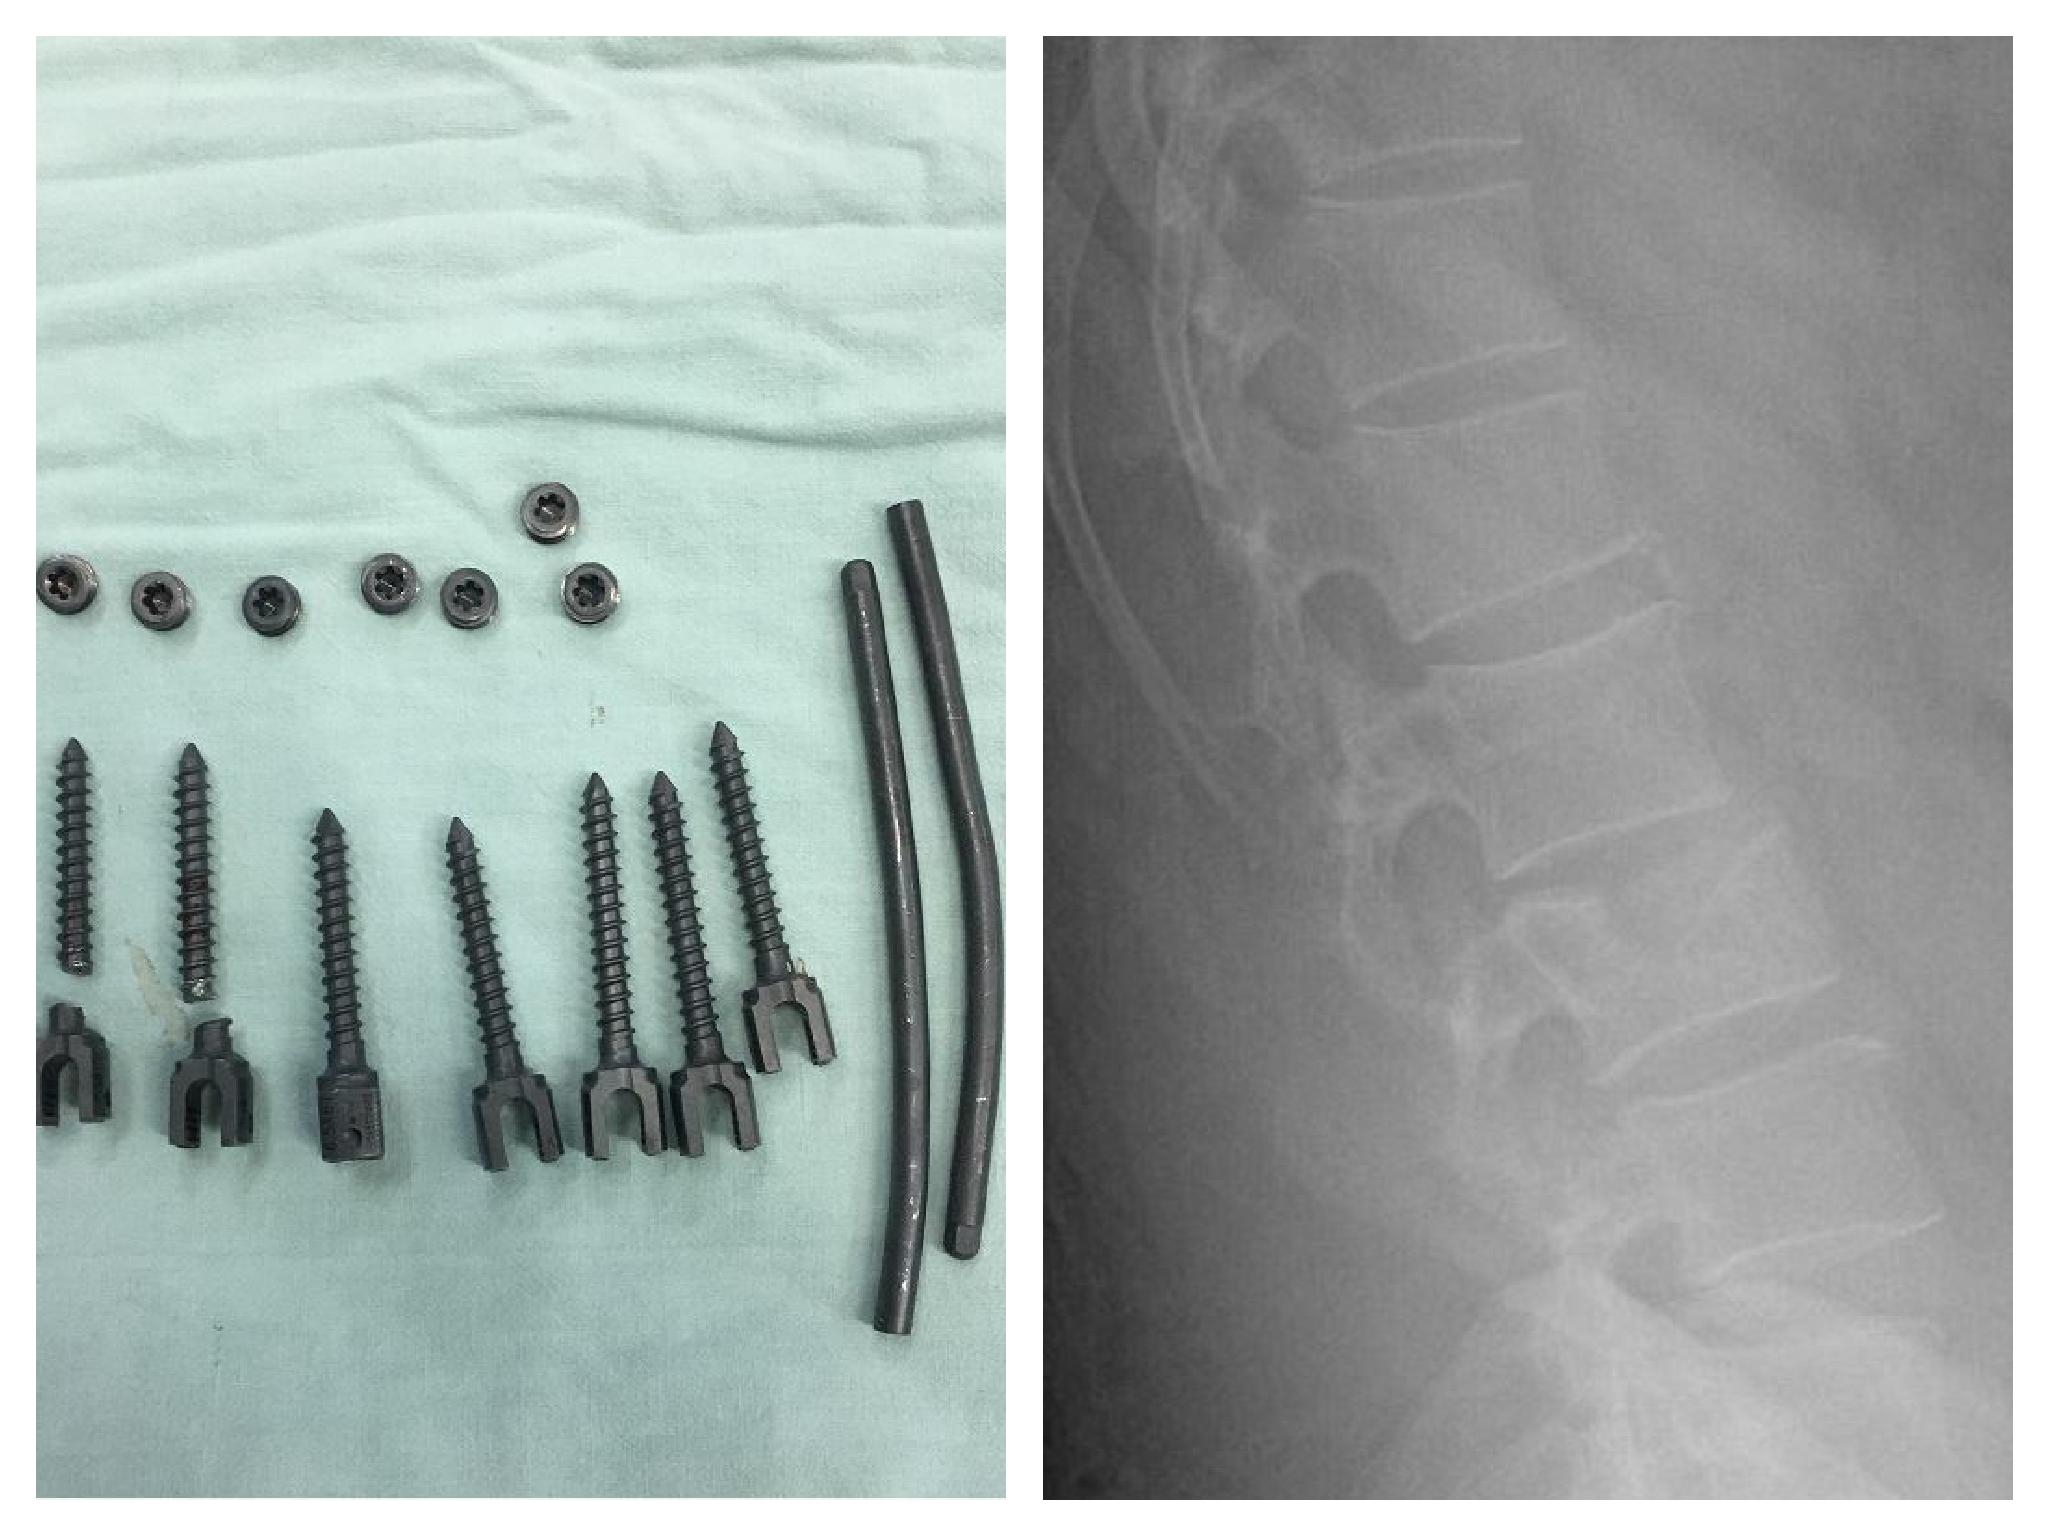

此次前来求医的患者患者杨某是武定县当地人,一年前因外伤致腰椎骨折住院,行腰椎椎弓根螺钉内固定术。近段时间老杨时常感到腰背疼痛,复查X片发现两枚椎弓根螺钉已经断裂。先后辗转昆明的多家三甲医院求诊却失望而归,面对这个烫手的山芋,医师接诊后给的建议都是最好不要取。

如果普通的钢板螺钉断裂,对于骨科医师而言不是难事,但椎弓根螺钉断裂就有着天壤之别,是骨科医师公认的“头痛事”。之所以骨科医师大都建议不要取,是因为椎弓根是人体脊柱稳定性最重要的结构,直径只有筷子粗细,断钉尾端看都看不到,又在切口的最深部,没有回旋操作的空间,要取出断钉又不破坏椎弓根,难度可想而知。如果为了取出断钉而把椎弓根的完整性破坏,反而得不偿失,手术本身就失去了意义。

但既然接了就绝不放弃不抛弃,在查找资料的同时,李慧章制定了缜密的治疗方案,并仔细推演了手术过程。为了有充沛的精力保证手术顺利进行,老杨的手术被特意安排在了当日第一台,各种环钻、断钉取出器、合适的钢丝等当地能准备的器械也都全部准备到位。功夫不负有心人,在全体医护人员的鼎力配合下,历时一个半小时,终于成功地全部取出了患者椎弓根内的两枚断钉。术后的李慧章终于长吁一口气,却忘记了早已湿透的手术衣。患者推出手术室的一刻,早已在门口忐忑等待的家属,脸上露出了惊喜的笑容。

术后复查CT显示患者断钉完全取出,椎弓根无明显损伤,手术非常成功。出院那天,老杨手捧一面大红锦旗,来到办公室连声道谢,“多亏上海来的专家,终于让我完成了心愿啊!”。李慧章却握着老杨的手同样感谢着他,“感谢你才是,是你坚定的信任和理解,给了我手术成功的底气和动力!”。